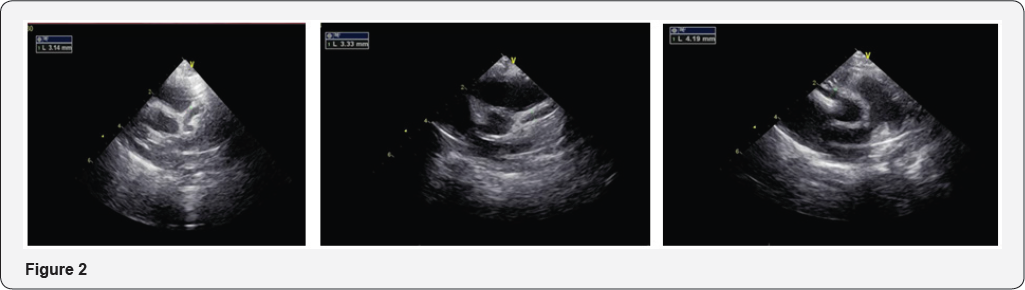

Echo cardiograph showed Dilated both coronary arteries with ectasia along the course of both coronary LCA 3.3-3.6mm, LAD 3 mm. aneurismal formation measuring 4.19mm at the origin of RCA (Figure 2).